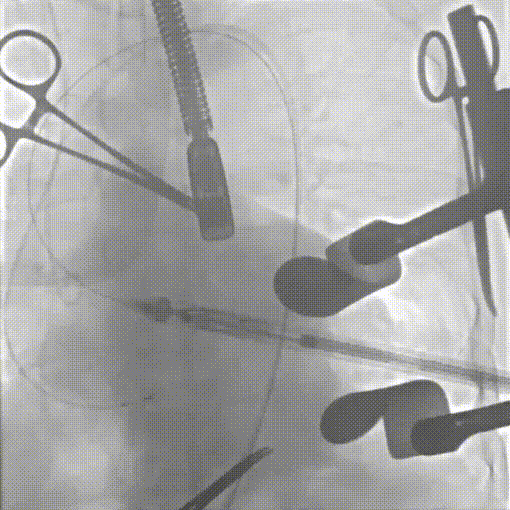

术前超声

术后超声长轴、短轴